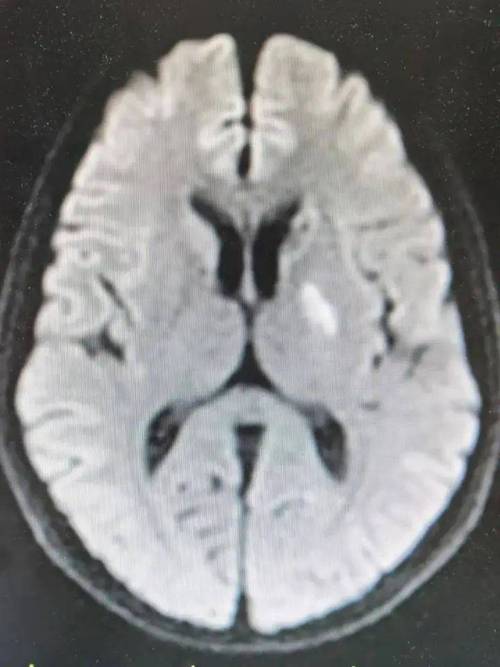

(图片来源网络,侵删)- 含义:这是“腔隙性脑梗死”的简称,这是一种缺血性脑卒中(也就是我们常说的“中风”或“脑梗塞”)的一种特殊类型。

- 形成原因:它不是大血管堵塞,而是由大脑深部穿通动脉的微小分支(直径通常小于2毫米)发生闭塞引起的,由于这些血管非常细小,堵塞后影响的脑组织范围也很小,会形成一个小的、空腔样的软化灶,所以被称为“腔隙性”梗死。

患者大脑右侧的基底节区域,发生了一个微小的血管堵塞,导致该区域的一小块脑组织缺血、坏死,形成了一个小软化灶(腔隙性梗死)。